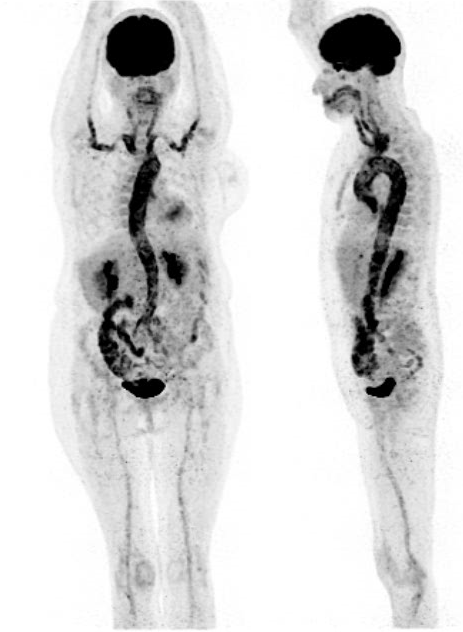

TEP au 18F-FDG chez une patiente présentant un syndrome inflammatoire inexpliqué. Mise en évidence d’une hyperfixation très intense des parois de l’aorte, en faveur d’une Maladie de Horton.